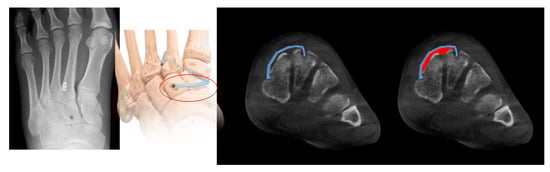

Radiological Evaluation: Radiographic measurements were performed preoperatively, immediately postoperatively, and at the final follow-up. Measurements were taken from weight-bearing AP foot radiographs (C1–M2 diastasis, side-to-side difference) and weight-bearing CT scans (dorsal and plantar diastasis).

Plantar Pressure Measurement: Plantar foot pressure analysis was conducted between 4 and 6 months postoperatively using a pedobarography system (Figure 3) (prior to hardware removal in the screw group) to assess dynamic foot function and weight distribution. Patients walked barefoot at a self-selected speed across the platform; three valid trials were recorded per foot, and peak pressure and force-time integral were calculated for predefined foot regions.

Figure 3. Comparison of foot pressure using pedobarograph with standard screw and internalbrace. Metatarsal foot pressure shows no different compare with contralateral foot in both group.

Plantar Pressure Analysis performed at 4 to 6 months after surgery showed no significant differences in peak pressure or force-time integral under the metatarsal heads when compared to the contralateral, uninjured foot in either group. This indicated a restoration of relatively normal weight distribution during gait for both fixation methods at this time point (Figure 3).